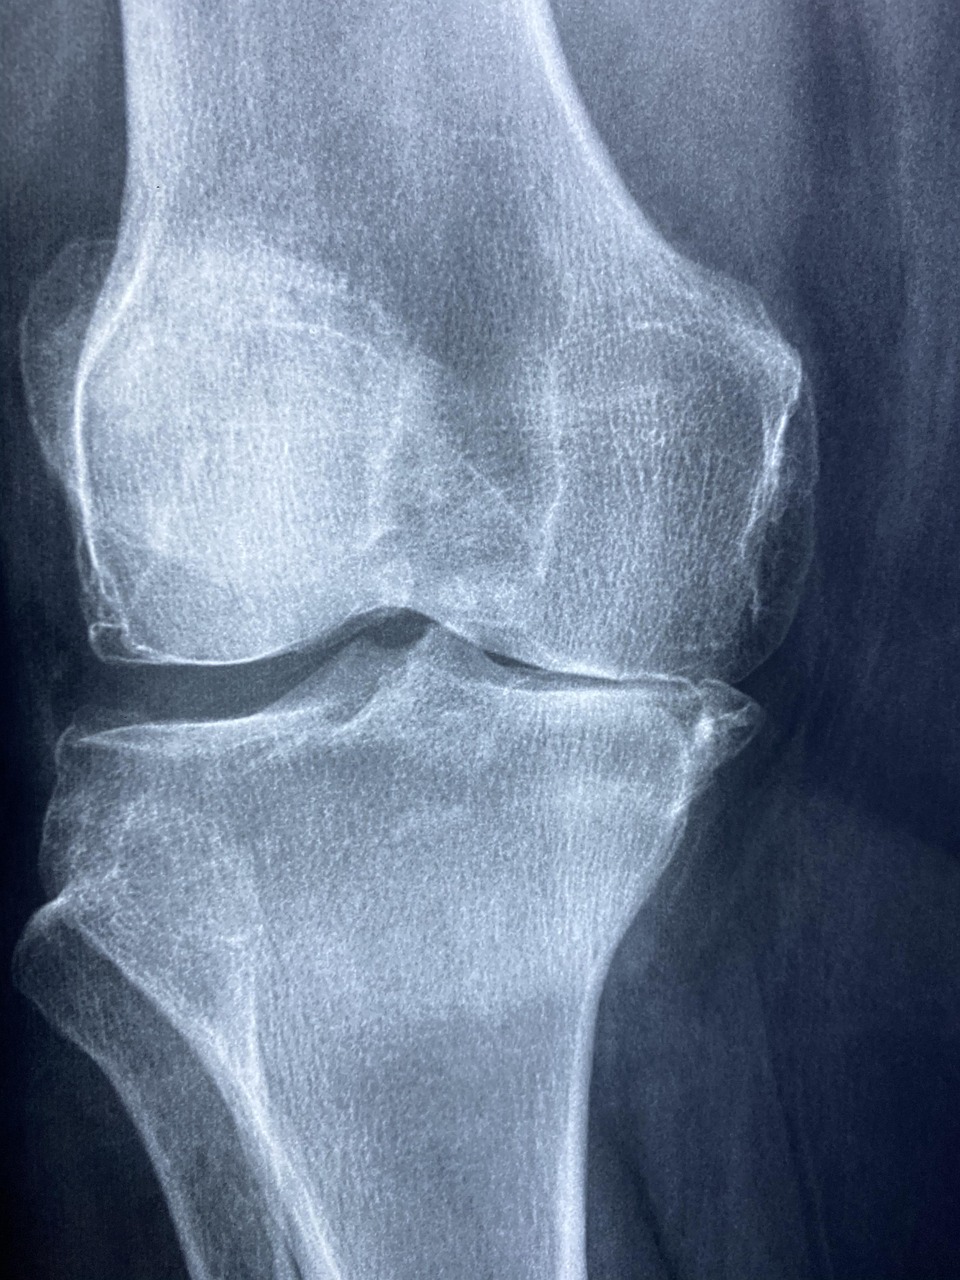

콘드로이친(Chondroitin)은 우리 몸의 연골, 뼈, 인대 등에 존재하는 중요한 성분으로, 관절 건강을 유지하는 데 핵심적인 역할을 합니다. 특히 연골을 탄력 있고 건강하게 유지시켜 관절이 움직일 때 충격을 흡수하고 마찰을 줄여주는 기능을 합니다.

일반적으로 해양 생물이나 동물의 연골에서 추출해 보충제로 활용하며, 관절염 예방 및 개선, 노화로 인한 관절 손상 완화에 도움을 줄 수 있습니다.

- 관절염 개선: 퇴행성 관절염의 통증 완화 및 진행 억제 효과.